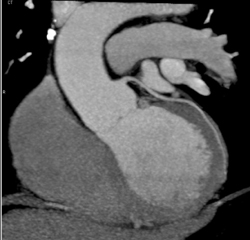

Normal Coronary Arteries